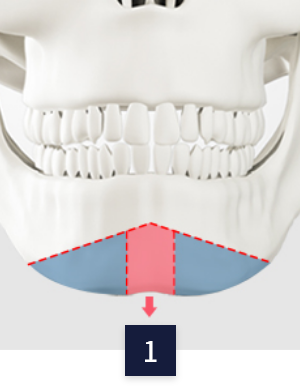

CASE 02

ㅅ절골

수술 방법

입안 절개

CT정밀검사로 턱 뼈와

신경선 파악 후 입안 절개

뼈 절제

중간의 턱 끝 뼈를

함께 절제

뼈 고정

나머지 절제된 뼈 고정 후

나머지 뼈 절제